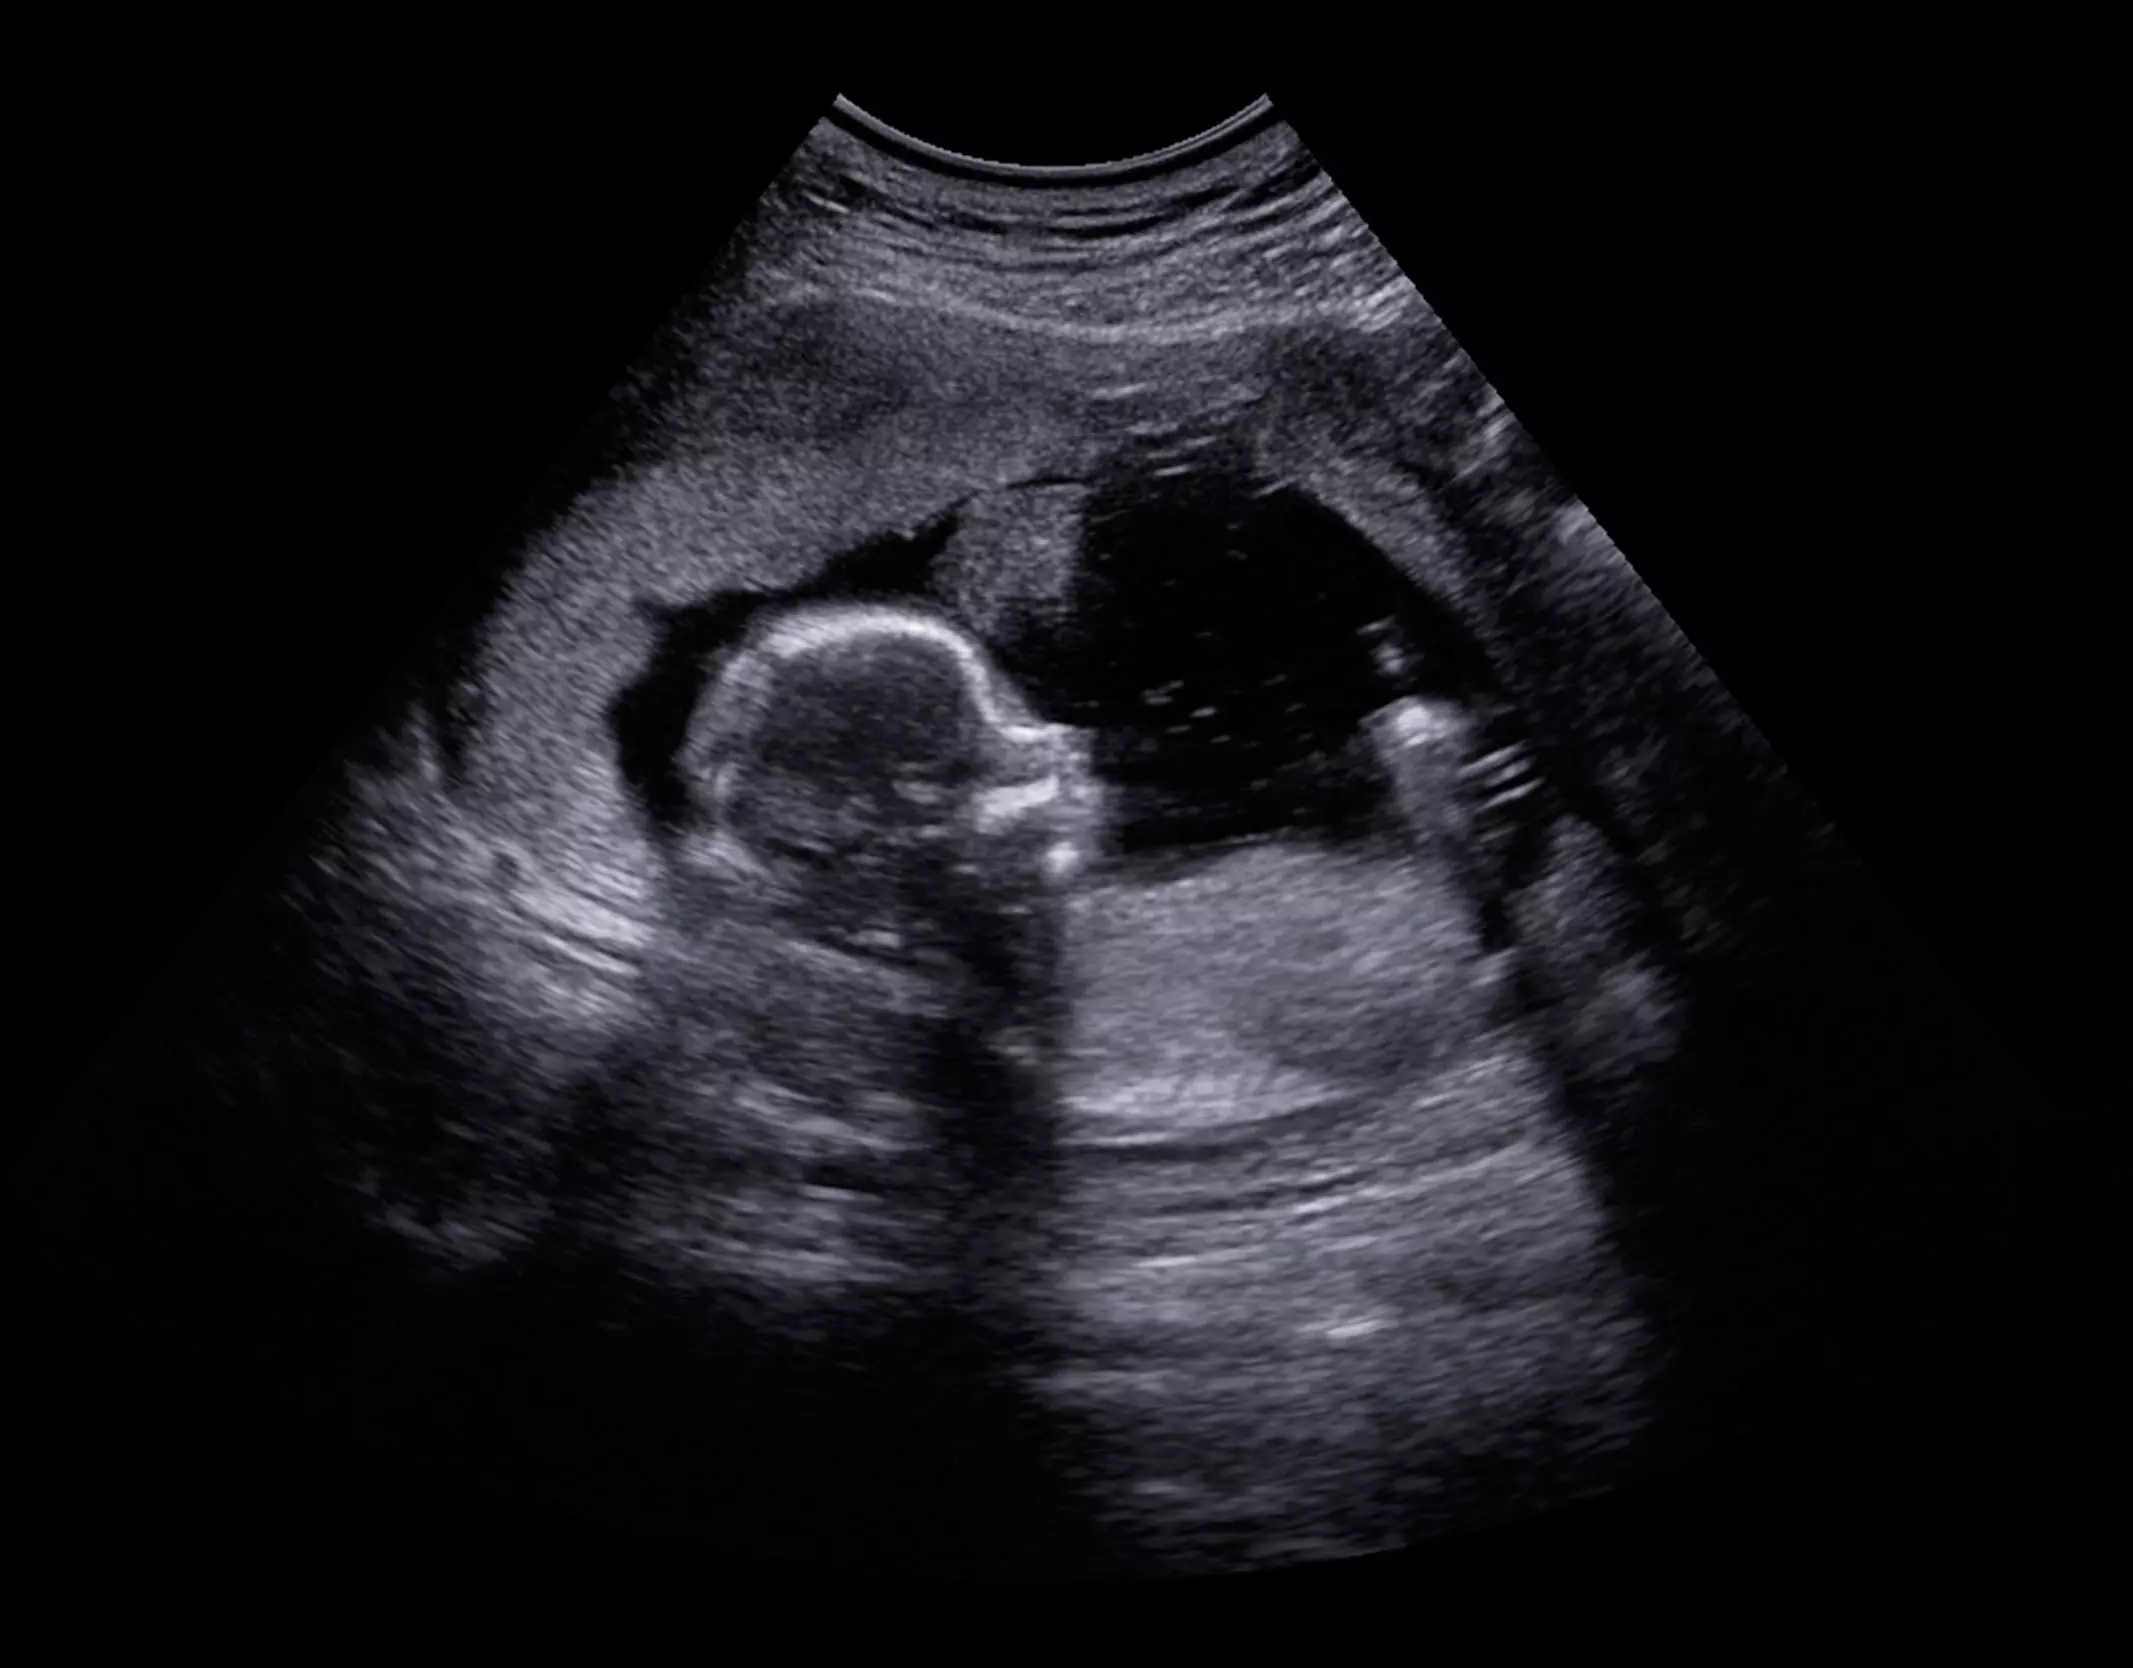

The abortion pill mifepristone (better known as RU-486) works by blocking the natural hormone progesterone that developing babies require to survive. APR consists of administering extra progesterone to counteract mifepristone’s effects, ideally within 24 hours of taking the abortion pill.